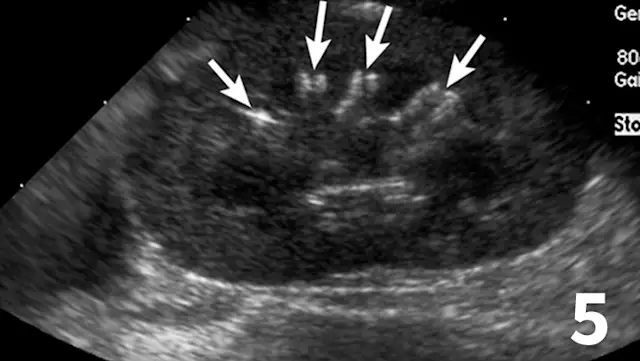

Similar to survey radiography, ultrasonography can document the number, size, shape, and location of the kidneys as well as the presence of mineralized tissue and nephroliths. In contrast to radiography, abdominal fluid or lack of abdominal fat does not limit the utility of ultrasound. The major advantage of ultrasound for evaluating kidney disease is its ability to assess the internal renal architecture and perirenal tissues. Both focal and diffuse lesions are recognized. Focal lesions may be solid, either homogenous or heterogenous, or fluid in nature. Diffuse lesions (Figures 4-8) may uniformly affect the parenchyma or be heterogenous. The renal cortex, medulla, or both regions may be affected depending on the disease process.